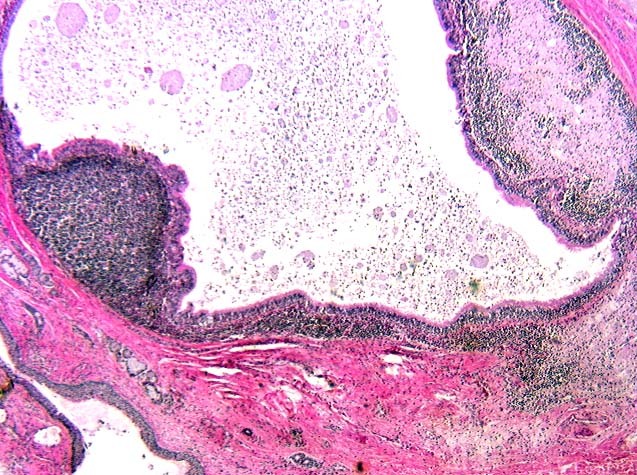

diagnosis?

immature teratoma

mature teratoma

define mature and immature teratoma

mature = benign, contain cell types from >1 germ layer

immature = malignant, mature cell type from all 3 germ layers and immature (embryonic, not foetal) tissue from at least one germ layer (usually neuroectoderm)